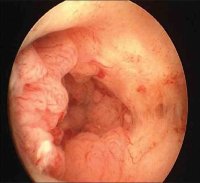

Ενδείξεις για υστεροσκόπησηΗ κύρια ένδειξη της υστεροσκόπησης είναι η ανώμαλη αιμορραγία της μήτρας, όπου απαιτείται εκτίμηση της παθολογίας της ενδομήτριας κοιλότητας και αποκλεισμός κακοήθειας. Μη φυσιολογική αιμόρροια μπορεί να είναι δυσλειτουργικής αιτιολογίας ή να οφείλεται σε ύπαρξη πολυπόδων , ινομυωμάτων, ξένου σώματος (κυρίως ενδομητρίων σπειραμάτων), σε χορήγηση ορμονικής θεραπείας υποκατάστασης σε γυναίκες μετεμηνοπαυσιακής ηλικίας, σε χορήγηση ταμοξιφαίνης ή σε παρουσία καρκίνου του ενδομητρίου. Με την υστεροσκόπηση η διάγνωση όλων αυτών των καταστάσεων γίνεται ευχερώς και με ακρίβεια υπό άμεση όραση, ενώ είναι δυνατή η εστιακή βιοψία, εάν υπάρχει ένδειξη. Η υψηλή ευαισθησία της μεθόδου της καθιέρωσαν ως τον "χρυσό κανόνα" στην διάγνωση των ενδομητρίων παθήσεων και τείνει να αντικαταστήσει την κλασική απόξεση του ενδομητρίου.

Σε περιπτώσεις υπογονιμότητας αποτελεί τη μέθοδο εκλογής τόσο για τη διάγνωση όσο και τη θεραπεία, διότι έχει βρεθεί ότι σε ποσοστό έως και 62% των υπογόνιμων γυναικών υπάρχει παθολογία της ενδομητρικής κοιλότητας. Υπερτερεί σαφώς της υστεροσαλπιγγογραφίας με άμεση διάγνωση των ενδομήτριων συμφύσεων, διαφραγμάτων, ινομυωμάτων, πολυπόδων αλλά και εκτίμηση της κατάστασης του ενδομητρίου. Αποτελεί επίσης σημαντικό εργαλείο στη διερεύνηση των καθ’έξιν αποβολών.

Η επεμβατική υστεροσκόπηση άνοιξε νέους ορίζοντες στην γυναικολογία. Πολύποδες, ινομυώματα τύπου Ι και ΙΙ εξαιρούνται με ασφάλεια με την χρήση ρεζεκτοσκοπίου ή υστεροσκοπικού ψαλιδιού, ενώ η νοσηρότητα είναι σημαντικά χαμηλή. Επίσης, σε περιπτώσεις συγγενών ανωμαλιών της μήτρας η υστεροσκοπική εξαίρεση των ενδομήτριων διαφραγμάτων υπερτερεί της κλασικής μητροπλαστικής. Μπορεί να γίνει με υστεροσκοπικό ψαλίδι, ακτίνες Laser, ειδικό εργαλείο versapoint ή ρεζεκτοσκόπιο. Με την ίδια τεχνική γίνεται και η λύση των ενδομήτριων συμφύσεων, εστιακών ή γενικευμένων. Μεγάλη είναι η συμβολή της επεμβατικής υστεροσκόπησης στην αντιμέτωπιση δυσλειτουργικών μηνομητρορραγιών με την καταστροφή του ενδομητρίου. Αυτή μπορεί να γίνει με Laser ή με την βοήθεια υστεροσκοπικού ηλεκτροκαυτήρα κινούμενης μπάλας ή αγκύλης που προσαρμόζεται στο ρεσεκτοσκόπιο.